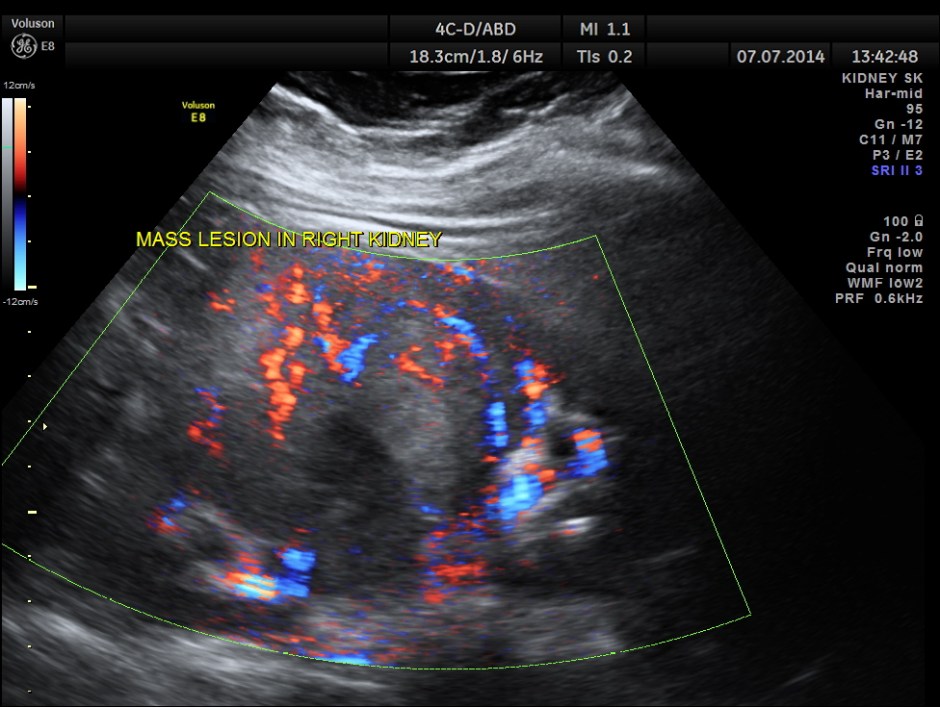

The right kidney is shown below. A solid mass is seen in the lower pole region.

The mass shows increased vascularity on Power Doppler.